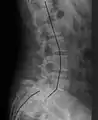

| X-ray of the lateral lumbar spine with a grade III anterolisthesis at the L5-S1 level. | |